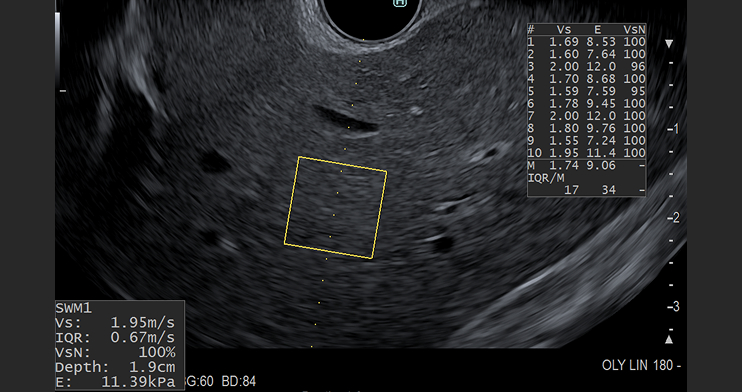

Optional features such as shear wave elastography, strain elastography and contrast harmonic imaging are available for the EU-ME3 and Aplio i800 EUS ultrasound processors. Click on each of the product links to learn more.

Now, due to recent advancements in endoscopic ultrasound (EUS), liver imaging, shear wave measurement, contrast harmonic imaging, liver biopsy and portal pressure gradient measurement can be accomplished under EUS-guidance.